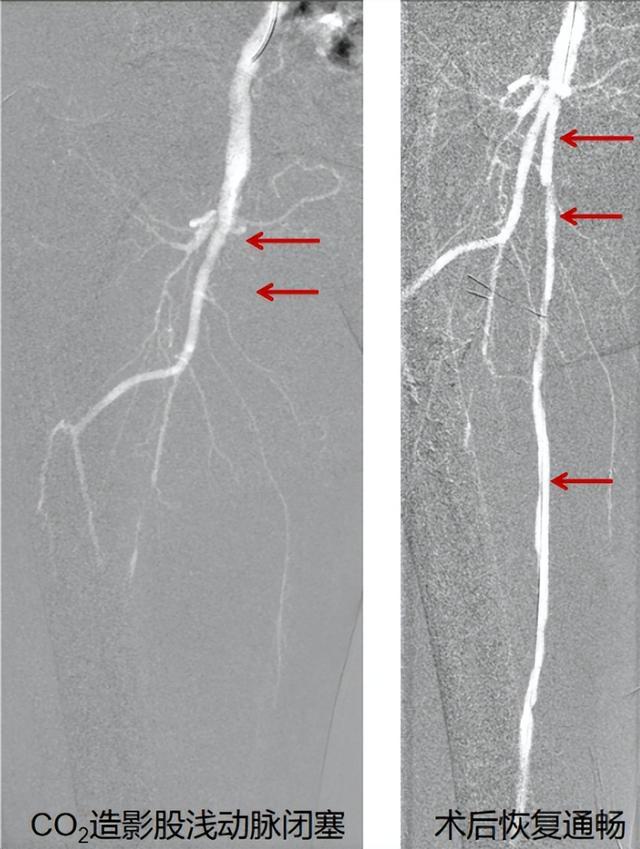

突破困局:株洲首台“二氧化碳造影”术

面对这一难题,株洲市三三一医院介入放射科章旭主任团队决定采用一项创新技术——二氧化碳(CO₂)数字减影血管造影。这也是株洲市首次将该技术应用于下肢动脉疾病诊断和治疗!

手术当日,医生从导管内注入CO₂替代碘剂,通过DSA设备实时显影。2个小时手术顺利完成,周爷爷完全闭塞的右侧股浅动脉顺利开通,术后疼痛症状消失,走两里路不费劲。更令人欣喜的是,他的肾功能指标在手术前后没有明显变化!